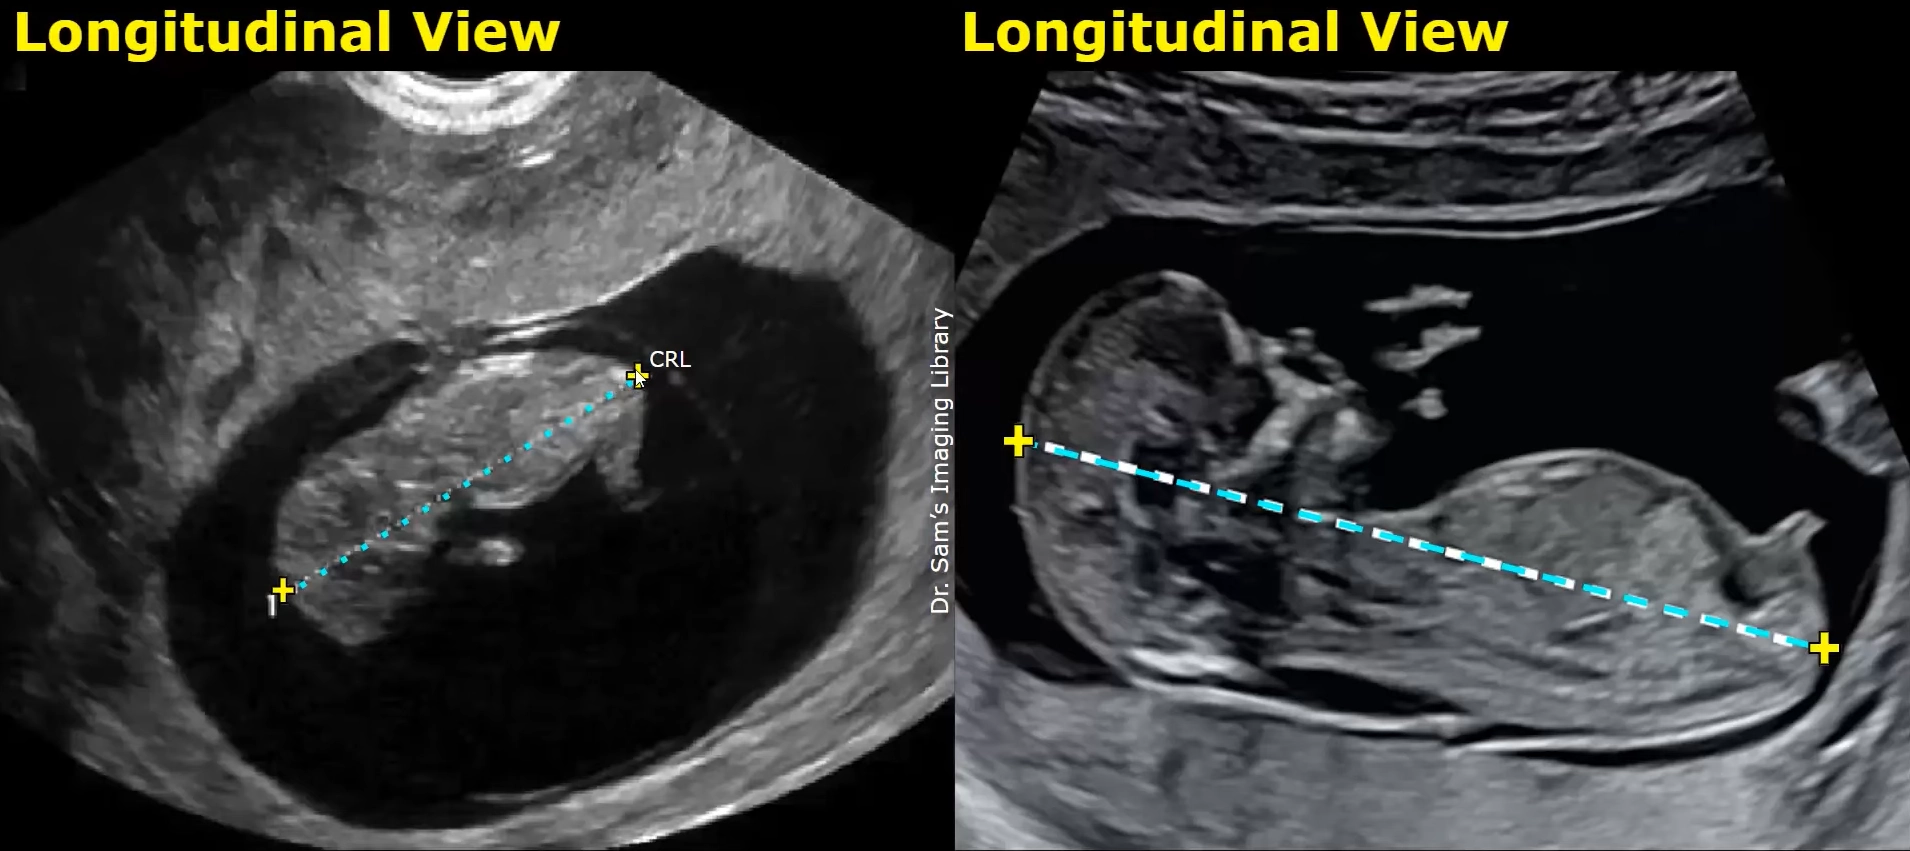

Sinh trắc học và xác định tuổi thai (biometry & dating)

• Sinh trắc học và xác định tuổi thai (biometry & dating)